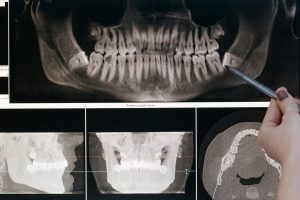

Diagnóstico